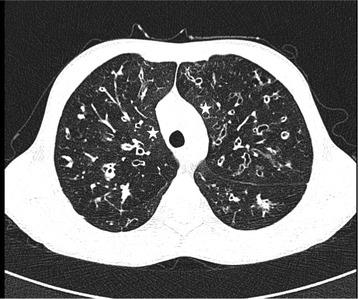

Bronchiectasis is a common feature of severe inherited and acquired pulmonary disease conditions. Among inherited diseases, cystic fibrosis (CF) is the major disorder associated with bronchiectasis, while acquired conditions frequently featuring bronchiectasis include post-infective bronchiectasis and chronic obstructive pulmonary disease (COPD). Mechanistically, bronchiectasis is driven by a complex interplay of inflammation and infection with neutrophilic inflammation playing a predominant role. The clinical characterization and management of bronchiectasis should involve a precise diagnostic workup, tailored therapeutic strategies and pulmonary imaging that has become an essential tool for the diagnosis and follow-up of bronchiectasis. Prospective future studies are required to optimize the diagnostic and therapeutic management of bronchiectasis, particularly in heterogeneous non-CF bronchiectasis populations.

支气管扩张症是严重遗传性和获得性肺部疾病的常见特征。在遗传性疾病中,囊性纤维化(CF)是与支气管扩张症相关的主要疾病,而获得性疾病常伴有支气管扩张症,包括感染后支气管扩张症和慢性阻塞性肺疾病(COPD)。从机制上讲,支气管扩张症是由炎症和感染的复杂相互作用驱动的,中性粒细胞炎症起着主要作用。支气管扩张症的临床特征和管理应包括精确的诊断性检查、量身定制的治疗策略和肺部成像,这已成为支气管扩张症诊断和随访的重要工具。需要前瞻性的未来研究来优化支气管扩张症的诊断和治疗管理,特别是在异质性非 CF 支气管扩张症人群中。